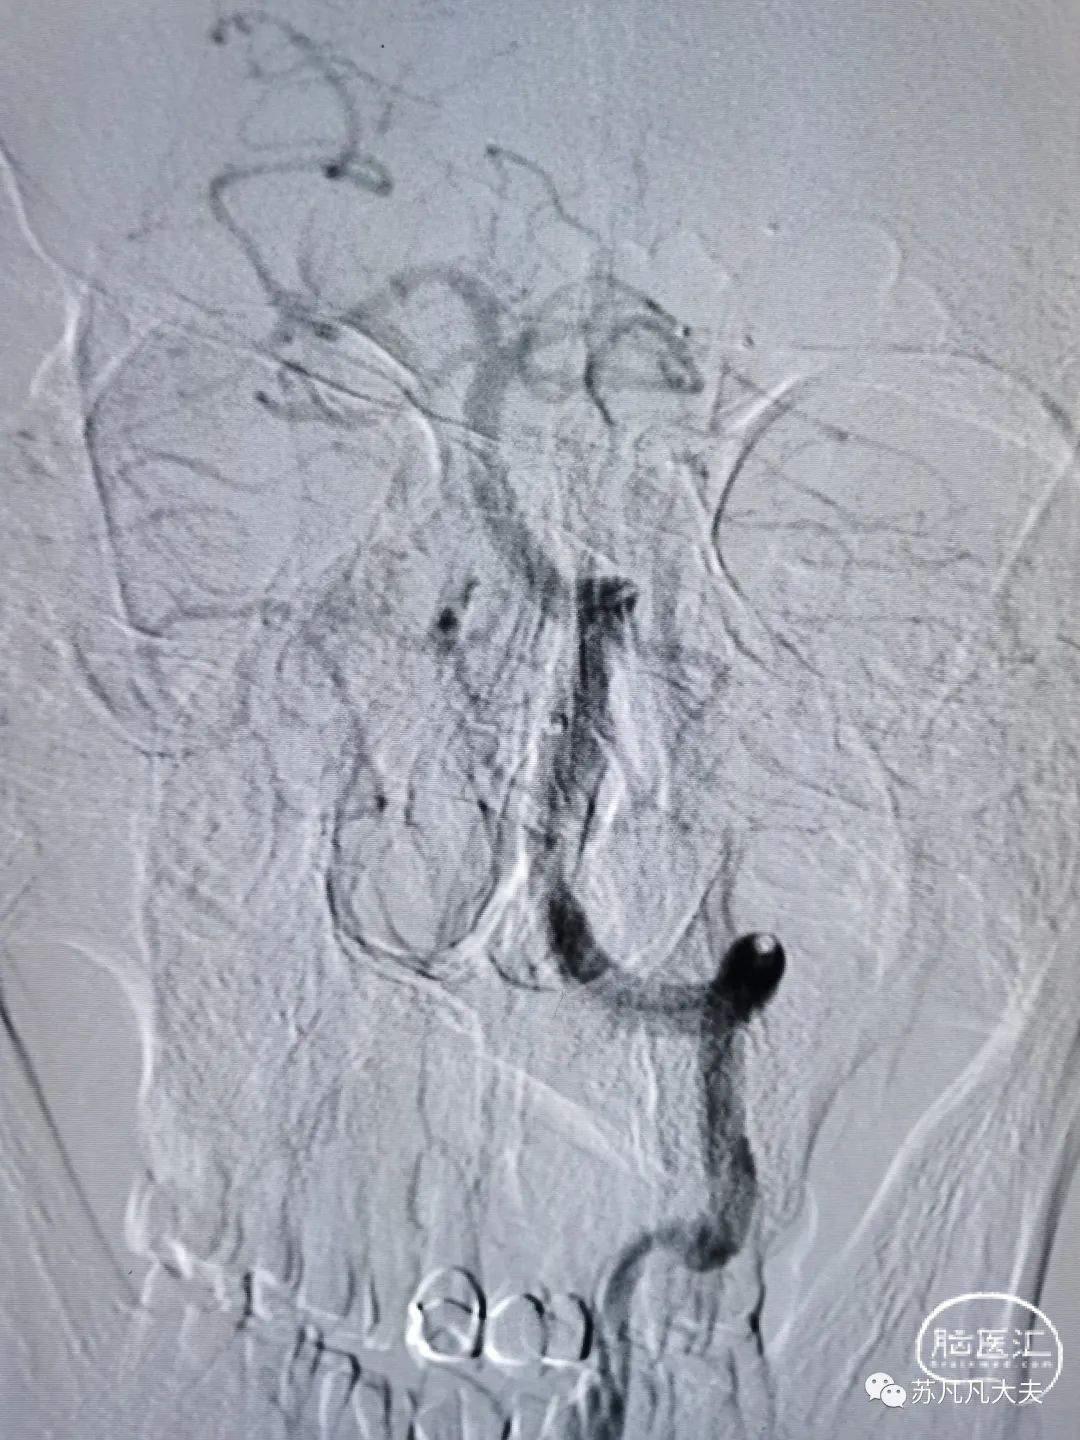

支架后颅内段狭窄解除

4/20取栓支架到位释放后造影

取栓后左侧大脑后动脉P1段再通